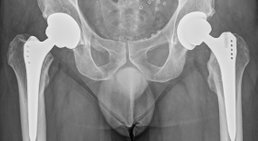

Als Facharzt für Orthopädie und Orthopädische Chirurgie habe ich mich auf die Behandlung von Verletzungen und Erkrankungen des Fußes, des Knies und der Hüfte spezialisiert.

Hüftprothese